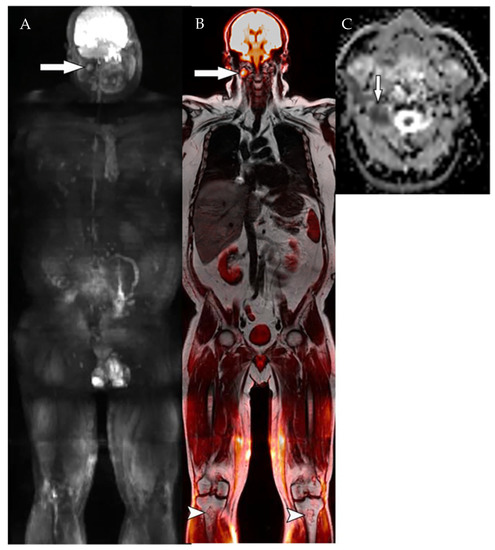

- Rasche, L.; Alapat, D.; Kumar, M.; Gershner, G.; McDonald, J.; Wardell, C.P.; Samant, R.; Van Hemert, R.; Epstein, J.; Williams, A.F.; et al. Combination of flow cytometry and functional imaging for monitoring of residual disease in myeloma. Leukemia 2019, 33, 1713–1722. [Google Scholar] [CrossRef]